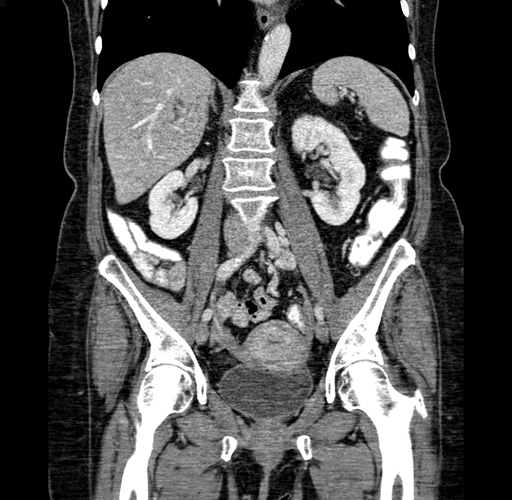

Pre-Chemo: Coronal Venous

Coronal Venous